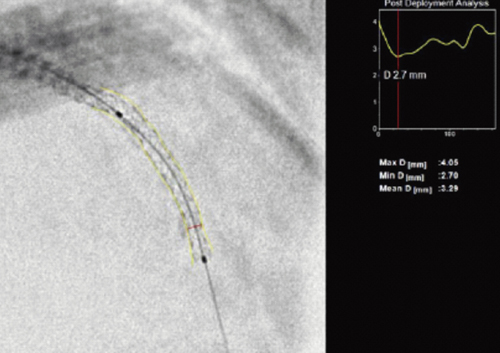

3.CV-3Dデバイス拡張評価ツール

デバイスの拡張不良によっても再狭窄は引き起こされるため,拡張デバイスの状態の評価は重要である。本ツールは,バルーンを留置したままの状態で,デバイス拡張後に収集した画像上の2つのデバイスマーカを指標として,収集画像の複数フレーム上のマーカ近傍にある画像領域に対して独自の画像処理を施し,デバイス以外の構造物や背景ノイズを低減させる一方で,その領域に存在する構造物(デバイス)のみを強調表示する。本ツールにより,透視だけでは判定し難かったデバイスの拡張度合いを,短時間で効果的に評価することができる。図5に,デバイスの強調表示の例を示す。デバイスの詳細な拡張状態が確認できる。

図5 CV-3Dによるデバイスの強調表示